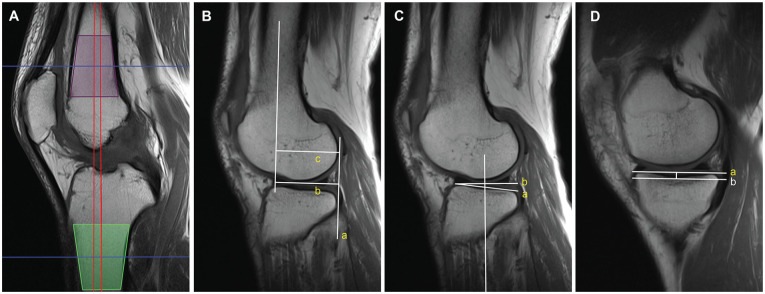

Methods: From the patients who visited the outpatient clinic of our hospital between 2012 and 2022, we included 78 patients with isolated PCL ruptures and 78 age- and sex-matched controls with knee injury but no structural damage evident on magnetic resonance imaging (MRI). The following parameters were assessed using MRI: the lateral femoral condyle and medial femoral condyle height and depth ratio (LFC-H/D, MFC-H/D), notch width index, intercondylar notch angle, the lateral tibial plateau slope, and medial tibial plateau slope (MTPS), and medial tibial depth. Values were compared between these 2 groups using the independent t test and the Mann-Whitney U test. Univariate logistic regression analysis was subsequently performed to identify independent risk factors. Receiver operating characteristic curves were generated for the morphological indicators and the combination of risk factors.